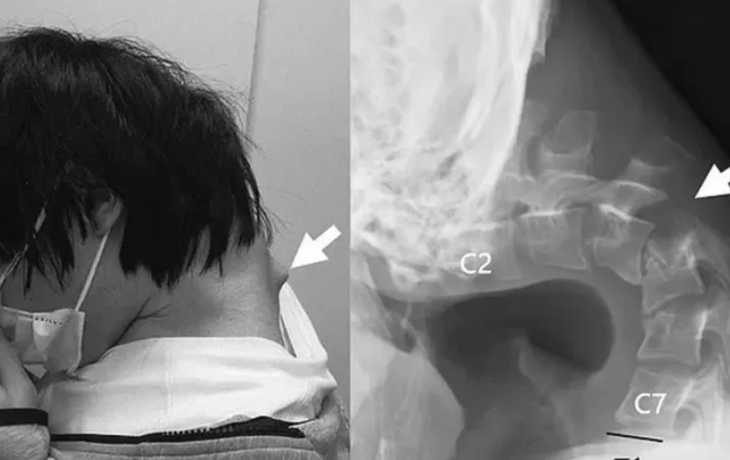

Phần cổ của nam thanh niên bị biến dạng sau thời gian dài cúi đầu để dùng điện thoại.

Nam thanh niên bỏ học và dành phần lớn thời gian trong ngày nhốt mình trong phòng, chơi điện thoại. Việc cúi cổ hàng giờ liền để nhìn xuống điện thoại đã khiến một khối u lớn hình thành ở phía sau cổ anh.

Chụp cắt lớp cho thấy đốt sống cổ của anh đã bị biến dạng và trật khớp, và mô sẹo đã hình thành ở cột sống trên do đã bị "kéo giãn quá mức" trong thời gian dài.